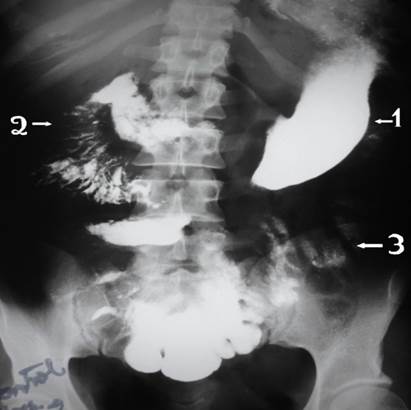

Se verifico el tránsito corto mediante estudio de tránsito baritado intestinal (Imagen 7,8.9)

Ilustración 7 Tránsito gastro-intestinal postquirúrgico; se verifica contraste que pasa desde duodeno al colon directamente

Fuente: Hospital de Especialidades Guayaquil “Doctor Abel Gilbert Pontón”.

Autor: Dr. Fernando Moncayo A.

Ilustración 8 Tránsito gastro-intestinal postquirúrgica, muestra anastomosis yeyuno-colónica.

Ilustración 9 Tránsito gastro-intestinal, muestra anastomosis yeyuno-colónica izquierda baja.